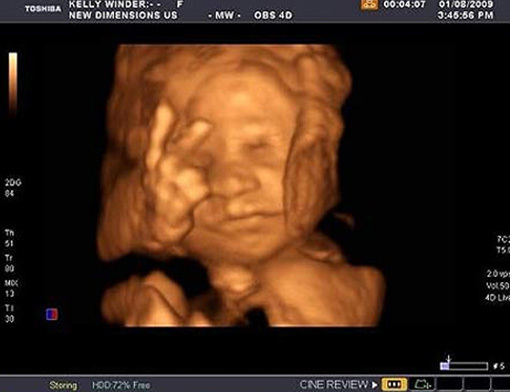

Cheeky Owen Patrick Skeffington dejó boquiabiertos a sus padres Kelly y Owen cuando en plena ecografía 4D, en la semana 27 de gestación, levantó sus dedos índice y corazón cantando victoria (o diciendo "yepp, aquí estoy...", o "paz, hermanos", o...).

El caso es que ante semejante gesto el médico pidió permiso a la pareja para hacer una copia y colgarla en la pared de su consulta y los padres decidieron hacerla pública para que todo el mundo la viera.